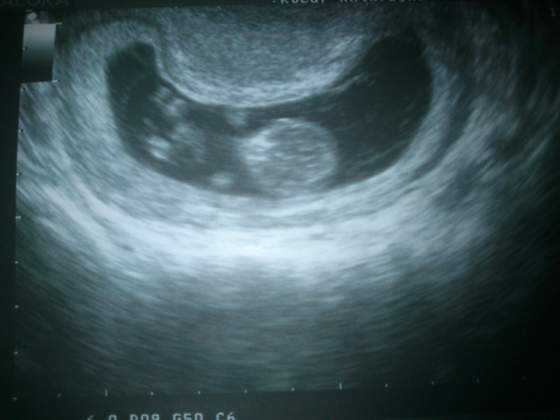

Ja wlasnie znalazlam chwile i zalaczam fotke mojej fasolinki: 4,5 cm szczescia)

Zobacz załącznik 508505